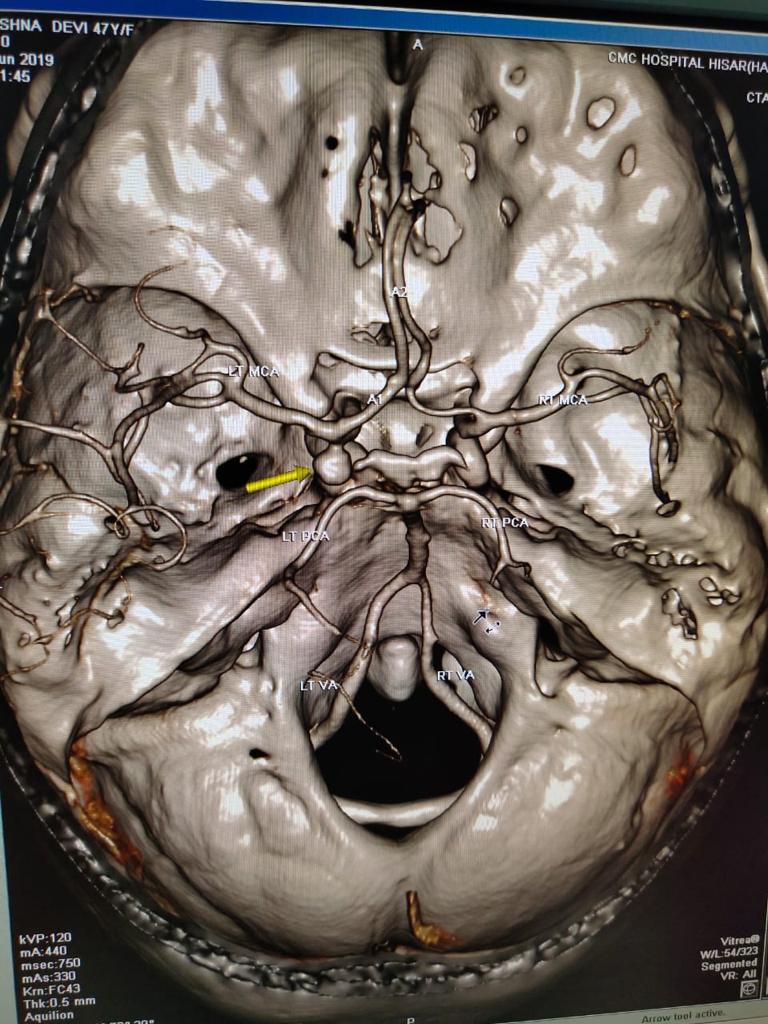

Cases